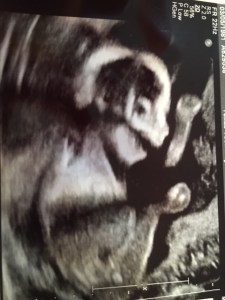

I’m five months pregnant! So far I have had two sonograms in which little Amaris Christinita was moving around like crazy! The machine has picked up her tiny fingers and toes, open mouth, and waving hands. Zooming in, the sonogram tech was able to distinguish the different parts of the brain, kidneys, bladder, and other organs. If there was any doubt that a baby existed in my growing tummy, it has been dispelled by undeniable pictures and movements!